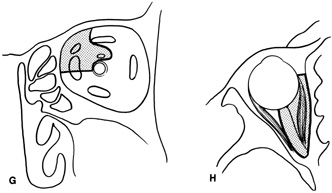

complete hemostasis. Indications Lateral orbitotomy provides excellent access to deep lesions in the subperiosteal, peripheral, or

intraconal space lateral to the optic nerve (Fig. 8A, B).  Fig. 8. Coronal (A) and axial (B) views in an illustration of areas (shaded) amenable to lateral

orbitotomy. Fig. 8. Coronal (A) and axial (B) views in an illustration of areas (shaded) amenable to lateral

orbitotomy.